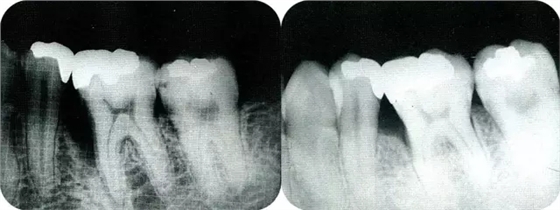

▲圖7-6再翻瓣半年之后的狀態(tài)。探診無出血,獲得了附著齦。

▲圖7-7術(shù)前,術(shù)后的x片。確認(rèn)出現(xiàn)骨再生,牙槽嵴硬線。